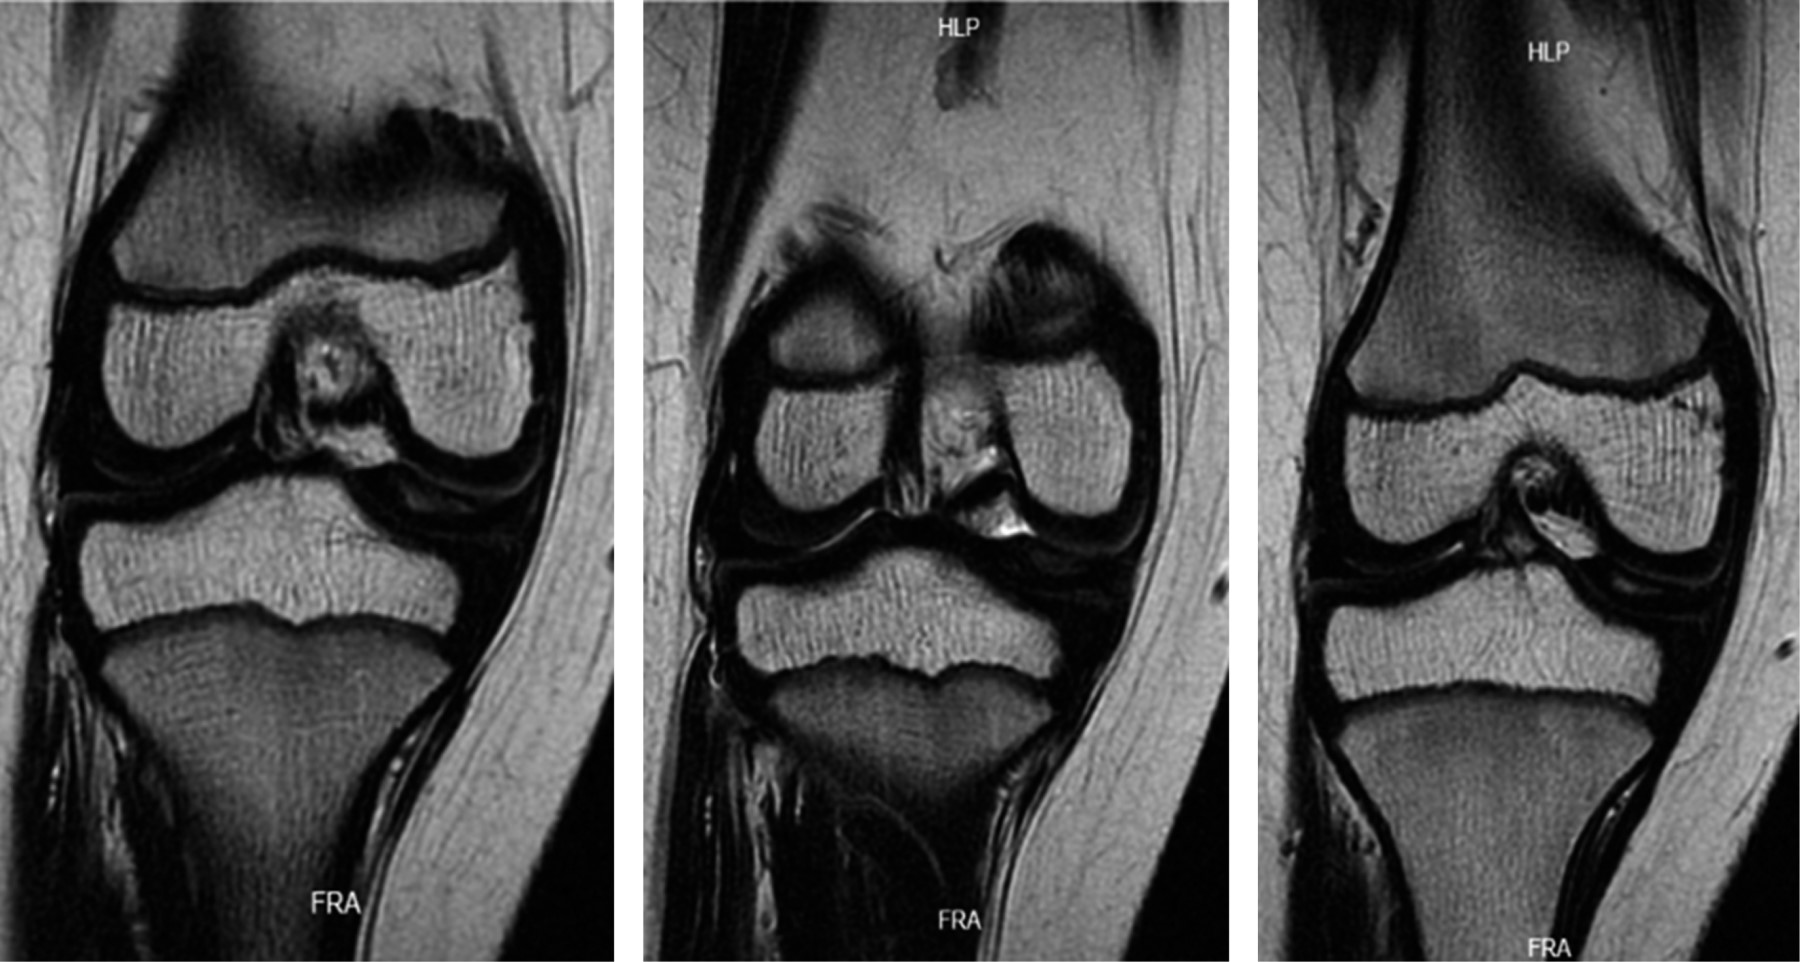

Se solicitó una resonancia magnética simple de la rodilla, que reveló una lesión de grado 3 en el menisco medial, bursitis suprarrotuliana y edema en los tejidos blandos de la parte anteromedial de la rodilla. Además, se identificó una lesión en el menisco medial con una morfología aparentemente discoidal, indicada por la presencia del "signo del corbatín" (Figuras 1 y 2).

Figura 1

Figura 2